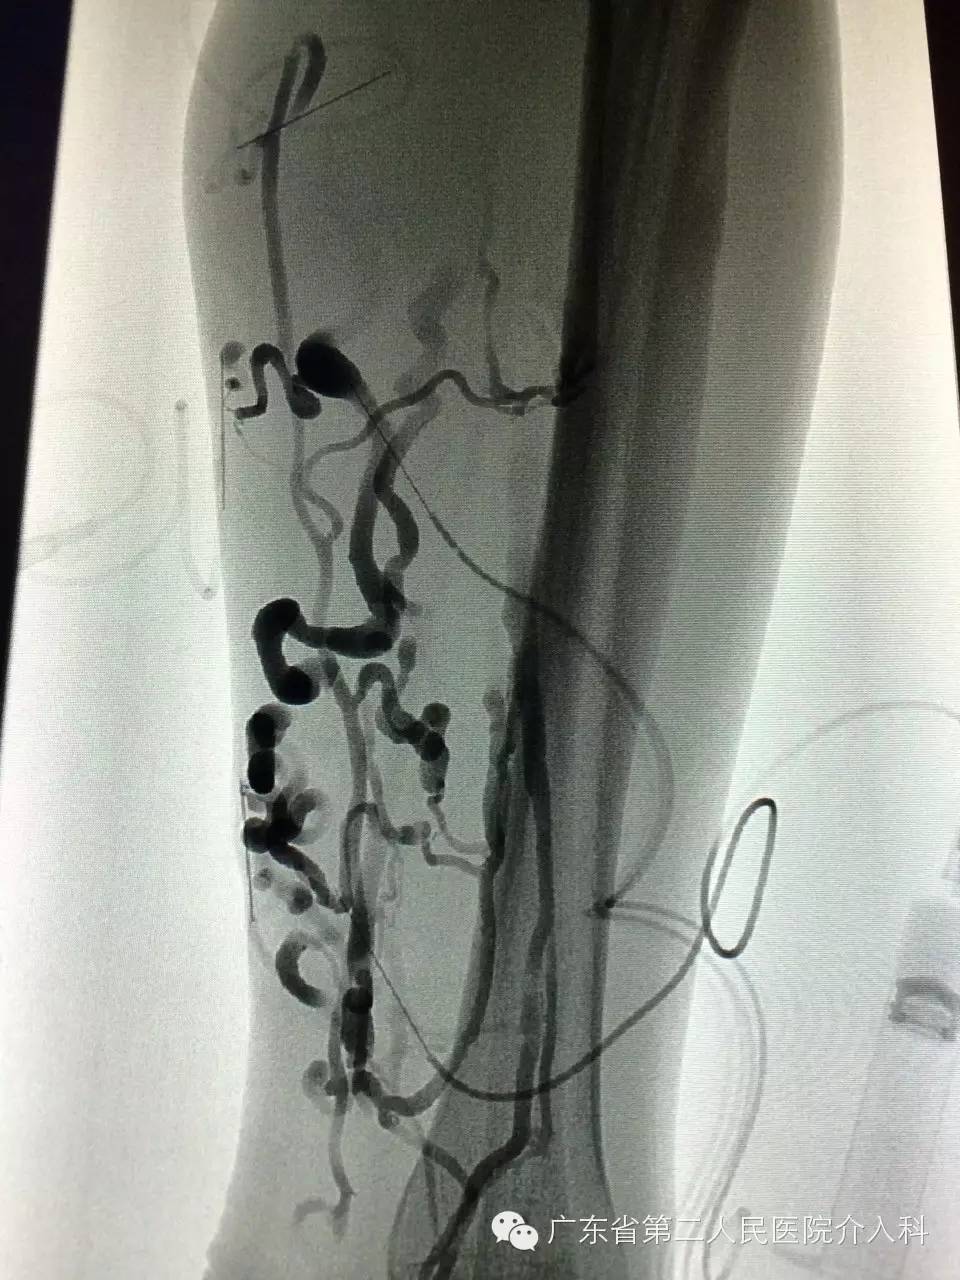

X线透视下行曲张静脉泡沫硬化剂注射治疗图